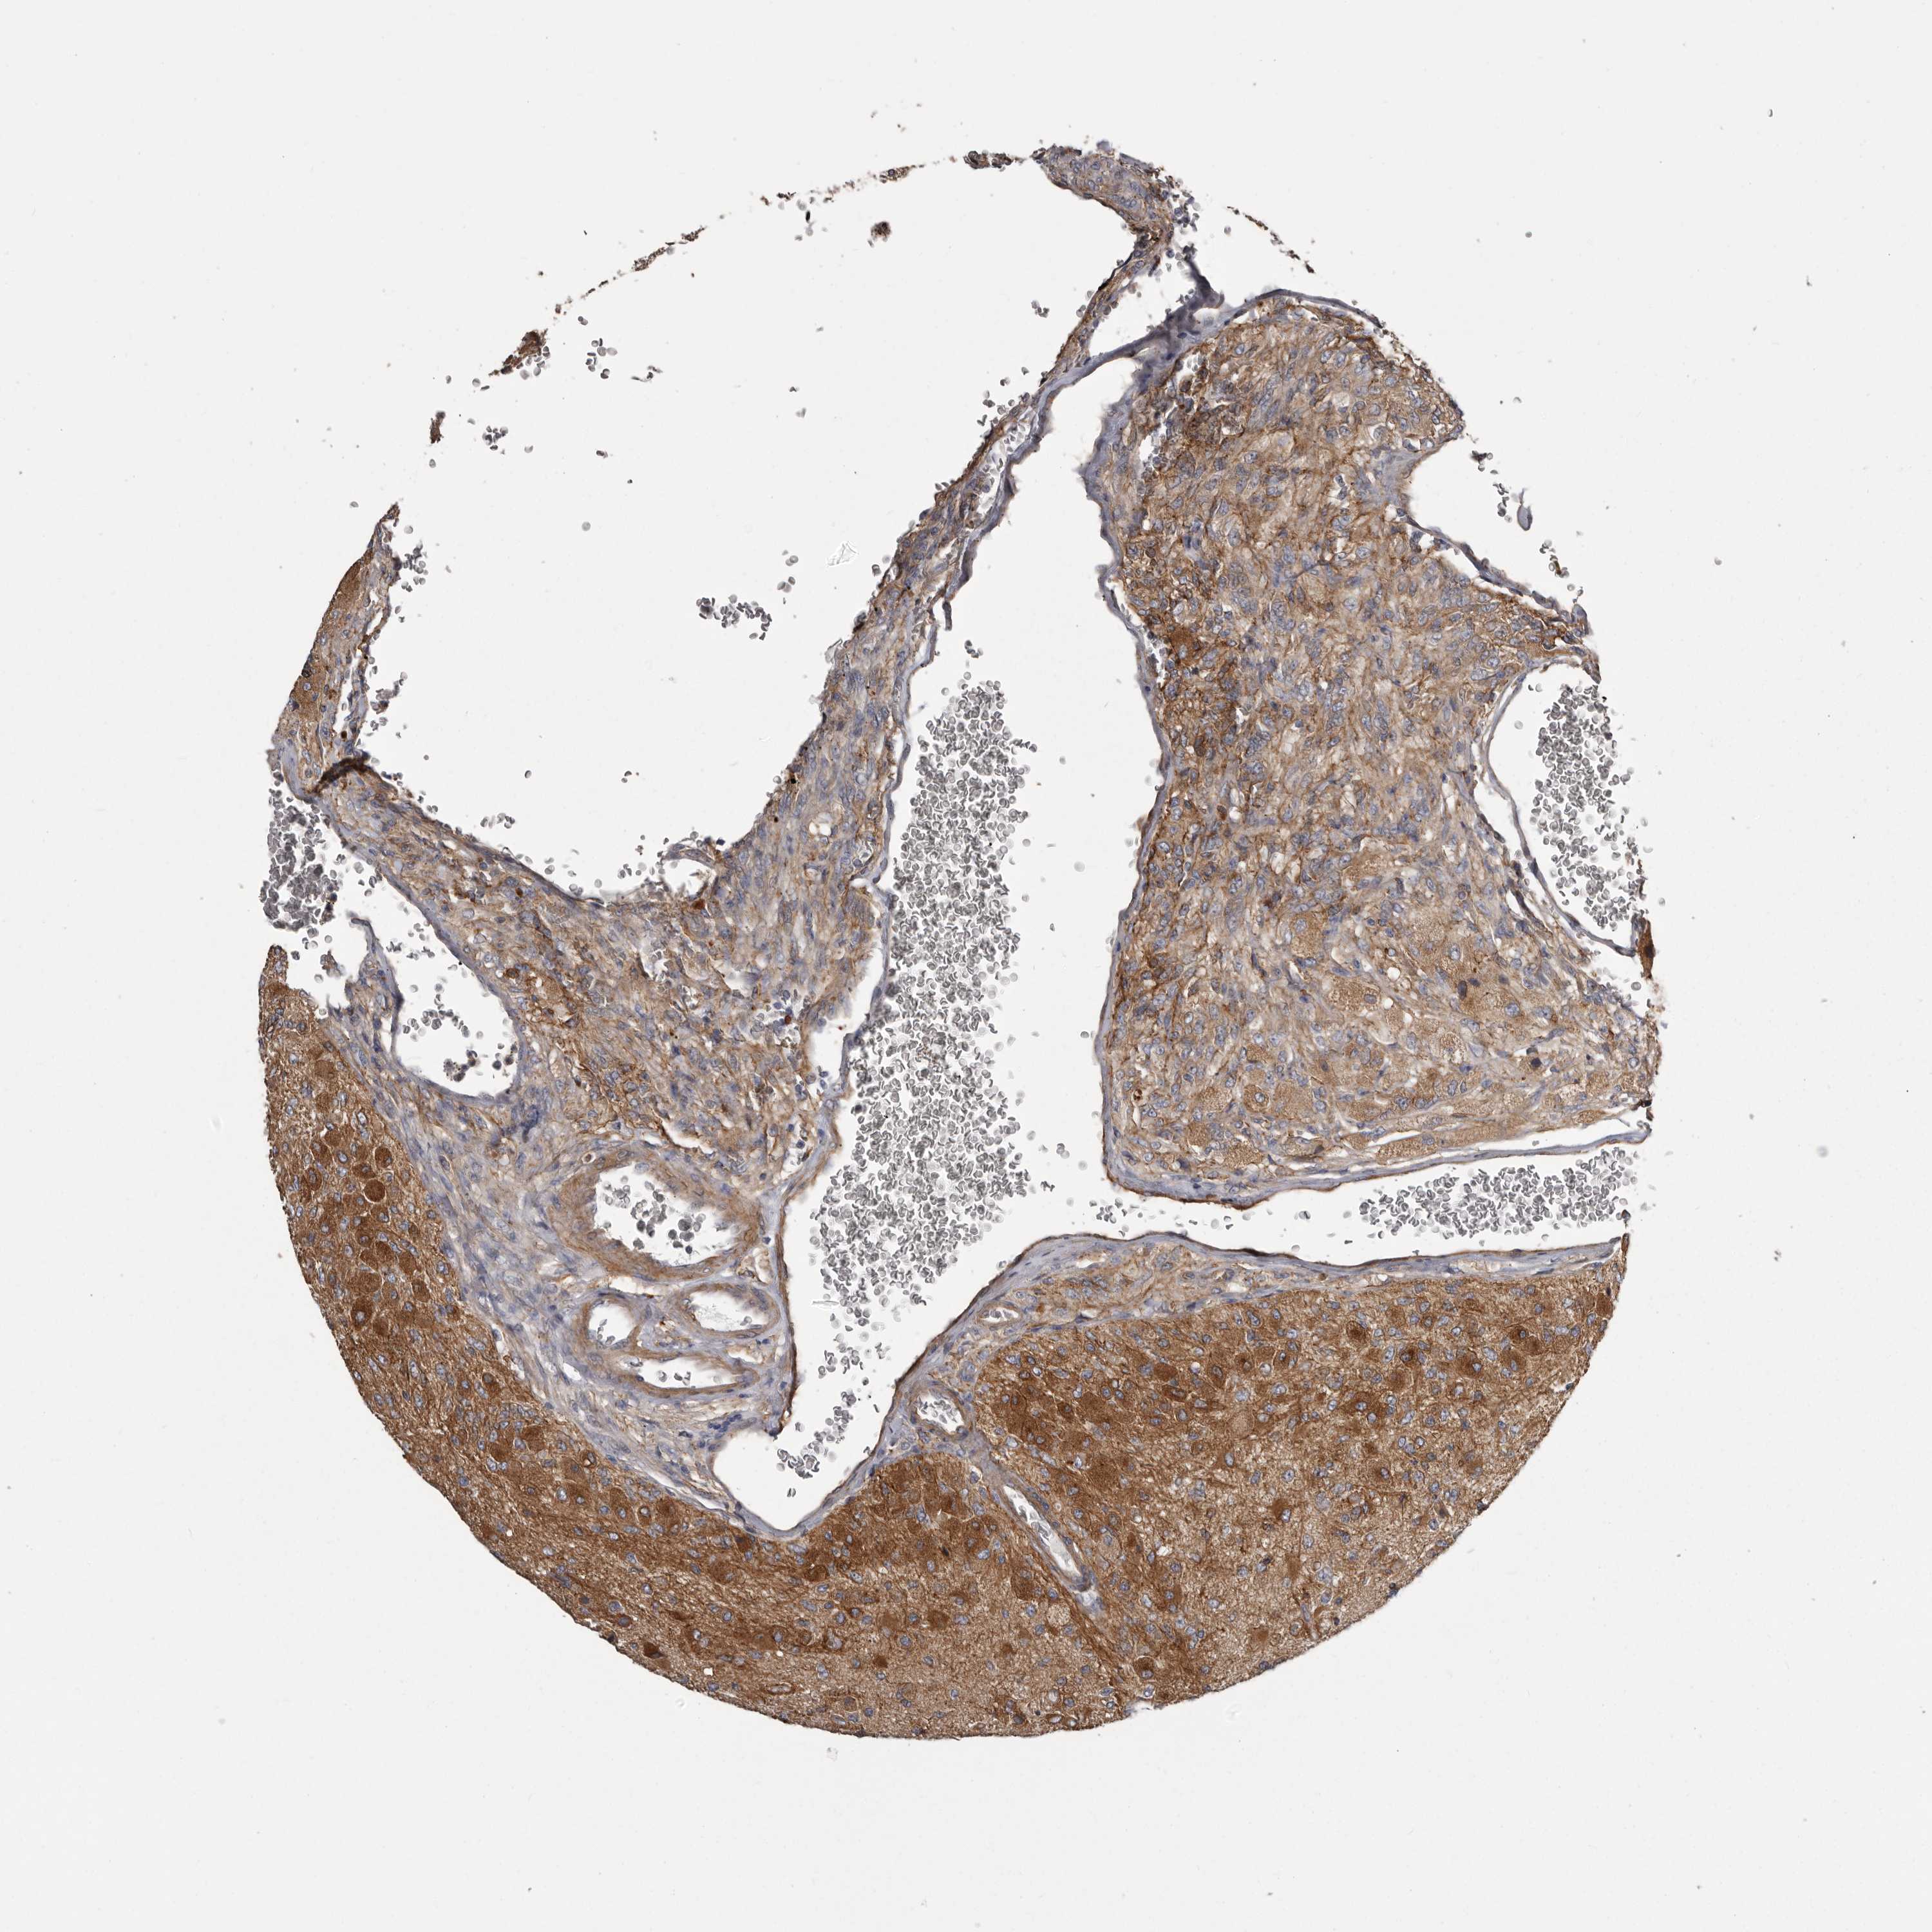

GLIOMA - Protein expressioni

A mouse-over function shows sample information and annotation data. Click on an image to view it in a full screen mode. Samples can be filtered based on level of antibody staining by selecting one or several of the following categories: high, medium, low and not detected. The assay and annotation is described here.

Note that samples used for immunohistochemistry by the Human Protein Atlas do not correspond to samples in the TCGA dataset.

Antibody stainingi

Antibody staining in the annotated cell types in the current human tissue is reported as not detected, low, medium, or high, based on conventional immunohistochemistry profiling in selected tissues. This score is based on the combination of the staining intensity and fraction of stained cells.

Each image is clickable and will lead to virtual microscopy that enables deeper exploration of all samples and also displays staining intensity scores, fraction scores and subcellular localization as well as patient and tissue information for each sample.

Antibody HPA028448

Antibody HPA028696

Glioma, malignant, High grade

Glioma, malignant, Low grade

Glioblastoma, NOS